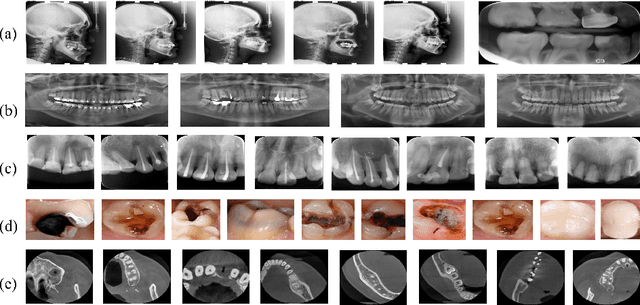

Abstract:Accurate tooth volume segmentation is a prerequisite for computer-aided dental analysis. Deep learning-based tooth segmentation methods have achieved satisfying performances but require a large quantity of tooth data with ground truth. The dental data publicly available is limited meaning the existing methods can not be reproduced, evaluated and applied in clinical practice. In this paper, we establish a 3D dental CBCT dataset CTooth+, with 22 fully annotated volumes and 146 unlabeled volumes. We further evaluate several state-of-the-art tooth volume segmentation strategies based on fully-supervised learning, semi-supervised learning and active learning, and define the performance principles. This work provides a new benchmark for the tooth volume segmentation task, and the experiment can serve as the baseline for future AI-based dental imaging research and clinical application development.

Abstract:3D tooth segmentation is a prerequisite for computer-aided dental diagnosis and treatment. However, segmenting all tooth regions manually is subjective and time-consuming. Recently, deep learning-based segmentation methods produce convincing results and reduce manual annotation efforts, but it requires a large quantity of ground truth for training. To our knowledge, there are few tooth data available for the 3D segmentation study. In this paper, we establish a fully annotated cone beam computed tomography dataset CTooth with tooth gold standard. This dataset contains 22 volumes (7363 slices) with fine tooth labels annotated by experienced radiographic interpreters. To ensure a relative even data sampling distribution, data variance is included in the CTooth including missing teeth and dental restoration. Several state-of-the-art segmentation methods are evaluated on this dataset. Afterwards, we further summarise and apply a series of 3D attention-based Unet variants for segmenting tooth volumes. This work provides a new benchmark for the tooth volume segmentation task. Experimental evidence proves that attention modules of the 3D UNet structure boost responses in tooth areas and inhibit the influence of background and noise. The best performance is achieved by 3D Unet with SKNet attention module, of 88.04 \% Dice and 78.71 \% IOU, respectively. The attention-based Unet framework outperforms other state-of-the-art methods on the CTooth dataset. The codebase and dataset are released.